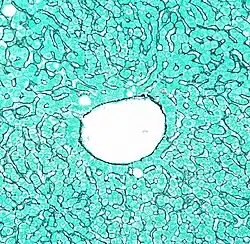

![]() La vena central intralobulillar, en el centro (marcada como a). | ||

Cada vena centrolobulillar, se encuentra en el centro de la estructura celular tridimensional, de forma prismática hexagonal llamada lobulillo.

La vena central de 150-200 μm de diámetro, está conformada por células endoteliales. Es sostenida por: una red laxa de delgadas fibras reticulares, por los cuerpos de hepatocitos adyacentes y por los sinusoides que desembocan en ella.[2][3]